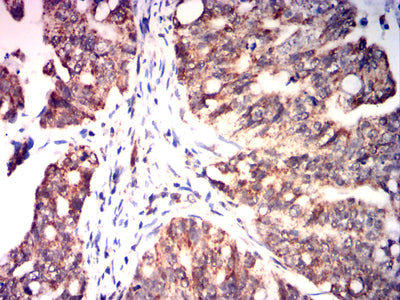

Immunohistochemical analysis of paraffin-embedded human cervical carcinoma tissues using ETFA mouse mAb with DAB staining.

Immunohistochemical analysis of paraffin-embedded human bladder cancer tissues using ETFA mouse mAb with DAB staining.

Immunohistochemical analysis of paraffin-embedded human breast cancer tissues using ETFA mouse mAb with DAB staining.

Immunohistochemical analysis of paraffin-embedded humanrectal cancer tissues using ETFA mouse mAb with DAB staining.